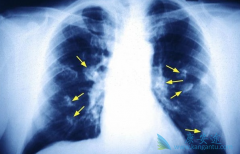

肺癌晚期的症状主要表现为声音嘶哑

众所周知,“谈癌色变”是很多人的第一反应。专家指出,对于恶性肿瘤,越早发现,越能增加康复治疗的概率。然而,对于肺癌而言,却总是发现的很晚。因此,了解肺癌晚期的症状就显得尤为重要,发现不及时也成为很多肺癌患者迁延难治的根本原因。那 肺晚期 ...